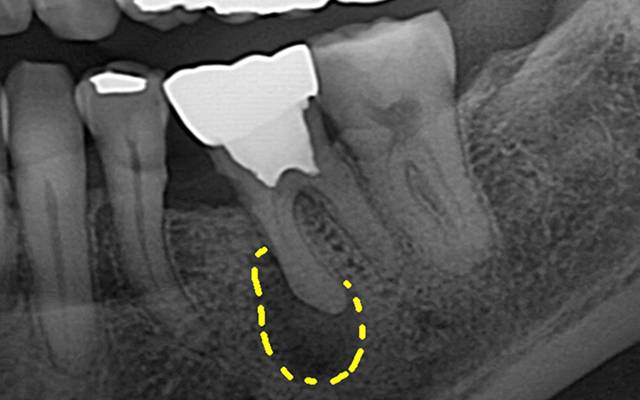

신경치료는 감염되거나 손상된 치수(신경·혈관)를 제거하고

뿌리관 내부를 소독·밀폐하여 치아를 기능적으로 보존하는 치료입니다.

감염 재발을 막기 위해 정밀 진단·무균 술식·밀폐가 핵심입니다.

| 진단·계획 | 치근단 엑스레이 기반 | CT 및 확대 시야 기반의 정밀 진단 |

심한 통증·냉온 자극 과민·자발통·뿌리부 염증(고름 주머니) 등이 의심될 때 권장됩니다.